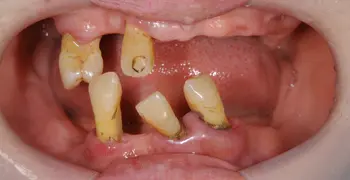

歯周病でほとんどの歯を失ってしまった場合は、総入れ歯による治療も考える必要があります。歯周病によってボロボロになった歯はグラグラと揺れている状態が多く、部分入れ歯の支えにするのが難しいことが多いです。

使用感が良くないと感じる人も多く、耐用性や見た目のことも考慮して、保険適用外の総入れ歯を選択する方もおられます。

虫歯・歯周病に関わらずほとんどの歯を失ってしまった場合、咬み合わせを一から計画してお口全体を治していく必要があり、このような治療はフルマウス治療と呼ばれます。

インプラントや矯正治療・被せ物などの複数の治療を駆使して進めるため高額にはなりますが、最終的な仕上がりを美しく機能的な歯にすることができます。